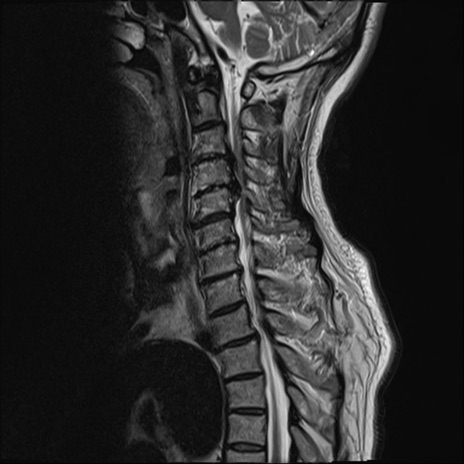

【整形】TIPS症例7 頚椎MRI T2WI(矢状断像)

頚椎MRI

矢状断像と横断像